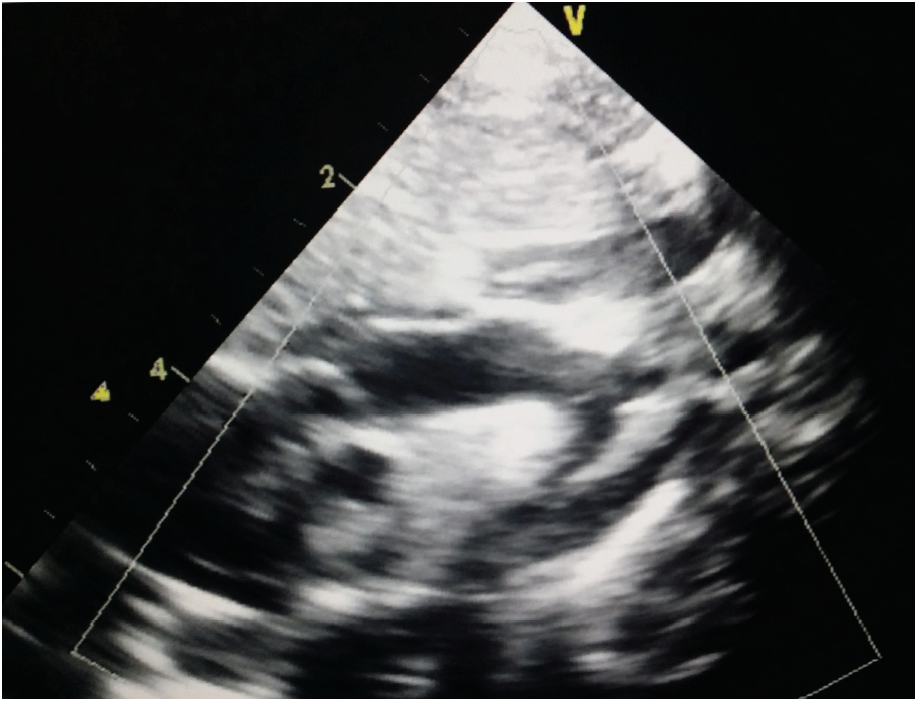

Sheela Madipelli, MD

The authors describe the case of a newborn who was completely asymptomatic, with normal results on CHD screening tests, normal femoral pulses, and normal perfusion, but with a significant systolic murmur. ...